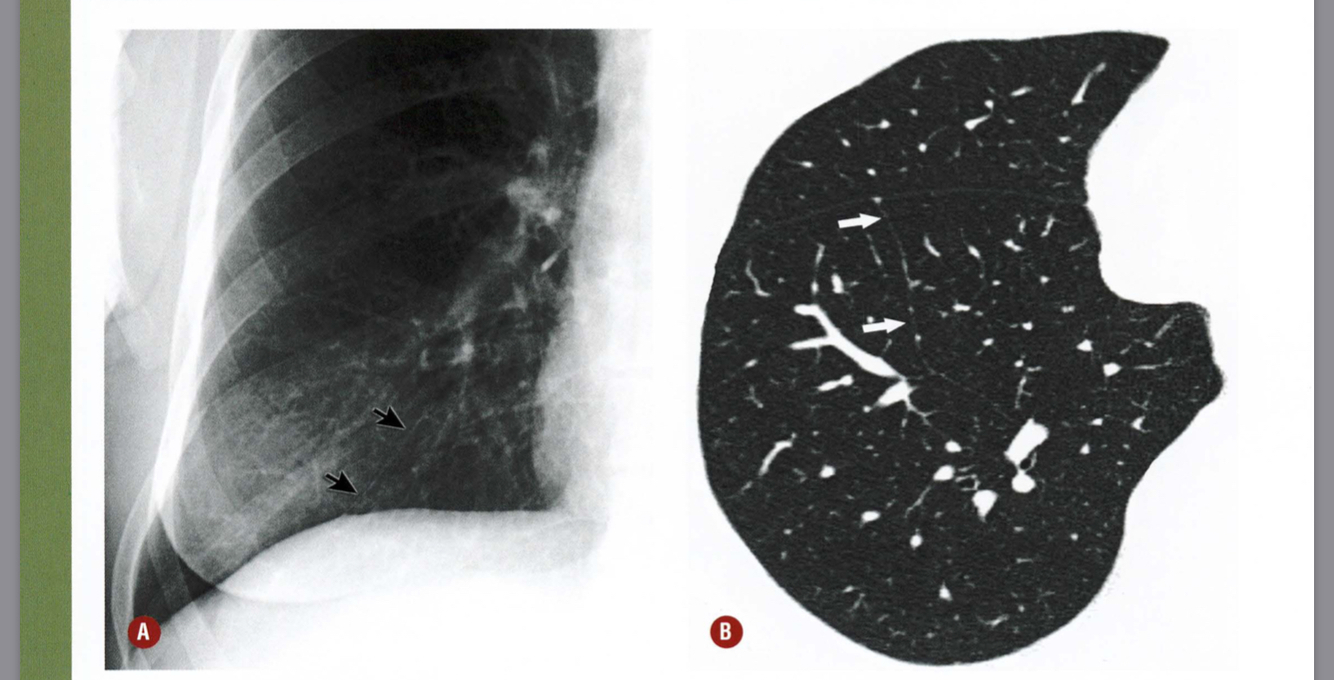

Qual a alteração demonstrada pelas setas?